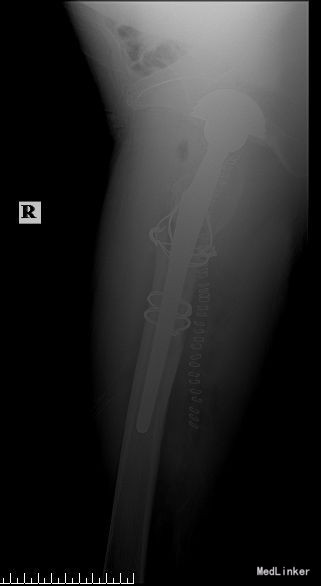

望:神志清,精神尚可,面色红润,营养良好,体型中等,舌红,苔薄黄;闻:语声清晰,呼吸均匀,未闻及特殊气味;切:脉弦紧。平车推入病房。右下肢较对侧未见明显短缩,外旋畸形,肌肉未见明显萎缩,右腹股沟饱满,腹股沟及大转子处压痛明显,右髋关节活动不能,“4”字实验因患者疼痛拒查,右下肢纵向叩击痛阳性,双下肢肌力未见明显异常。双下肢皮肤感觉未见明显异常,末梢血液循环尚可。X线检查:右侧人工全髋关节置换术后假体周围骨折。

术后复查X线片示假体位置良好,固定牢靠。根据中医辨证论治:中医辨病辨证依据:该病因直接暴力作用,致骨挫筋伤,而致气滞血瘀,经络受损,瘀阻经络,证属气滞血瘀。舌质淡,苔薄白为病邪尚未入里,脉弦,主瘀,主痛,亦为“气滞血瘀”之征象。术后嘱患者中医调护:避风寒,调饮食,慎起居,畅情志;保持切 口清洁,预防感染,注意饮食营养,多吃蔬菜、水果及含蛋白质高的食品,不能进食辛辣刺激类食物。继续口服药物治疗。继续抗炎、抗凝、抗骨质疏松治疗,预防关节术后并发 症;如遇身体局部及全身感染,及时就诊,继续口服利伐沙班或阿司匹林预防血栓性疾病。药物对症处理,适当功能锻炼,主动被动进行关节的 伸直,弯曲,直腿抬高训练,促进关节功能恢复;积极治疗内科基础病,控制血压,预防内科并发症,复查切口愈合情况。避免跪姿,跑跳,深蹲等剧烈活动,按时复诊;助行器使用到复查。不适随诊。本病例中医药应用结合手术治疗,可迅速缓解患者症状,恢复患肢功能,加快术后恢复,可使患者获得满意的术后疗效。